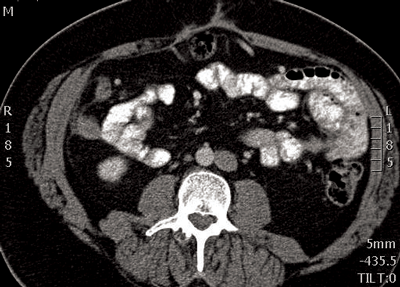

Figure 4: Retroaortic left vein seen posterior to the aorta.

Retroaortic renal vein (Figure 4)

This is less common than the circumaortic renal vein, with a prevalence of 2.1%. The left renal vein passes posterior to the aorta and drains into the lower lumbar aspect of the IVC, or more rarely the common iliac vein [1,5].